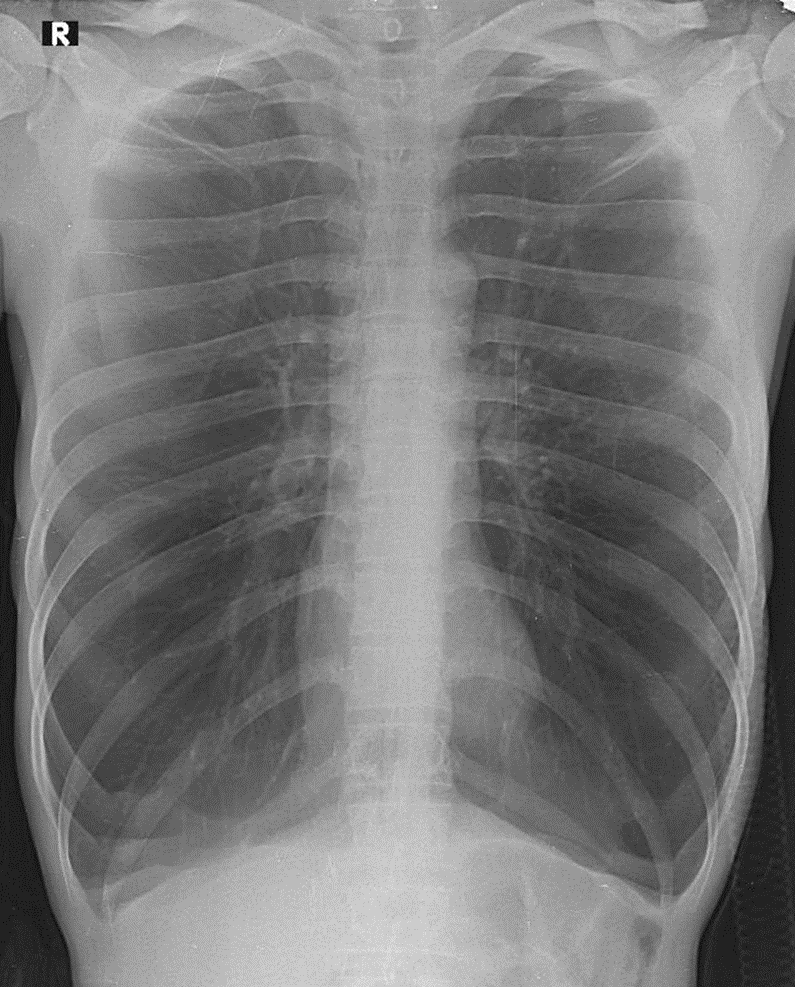

Hãy phân tích tình huống NAM 41 tuổi -CĐ:Suy hô hấp hổn hợp, đợt cấp COPD, viêm phổi cộng đồng

1-Khí phế thũng rải rác hai phổi 2-Bóng tim nhỏ